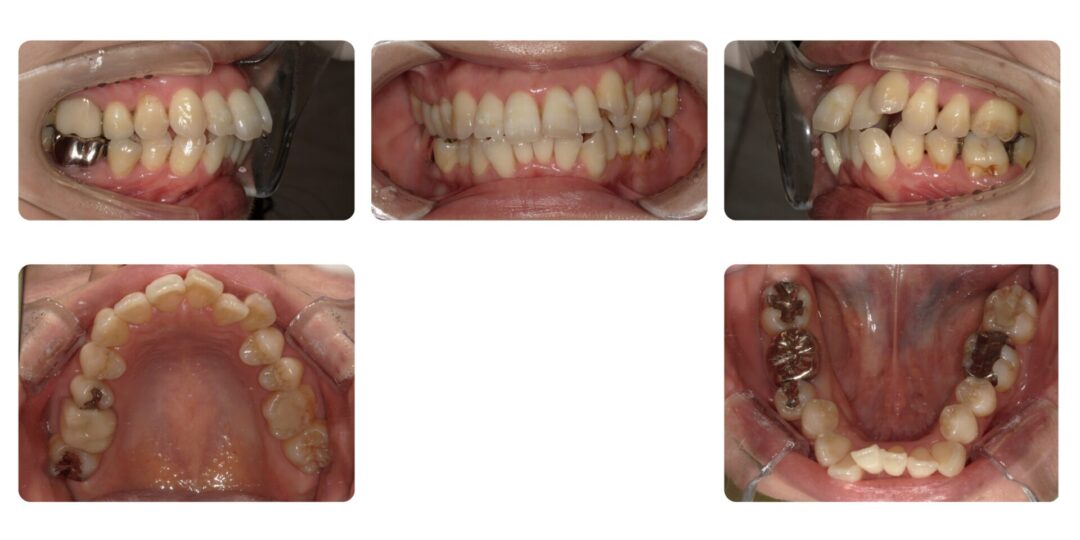

上下顎前歯唇側傾斜を伴う骨格性上顎前突|初診時28歳

上の前歯が前に出ている、八重歯

成人矯正 上下顎左右4番抜歯 マルチブラケット装置による歯列矯正